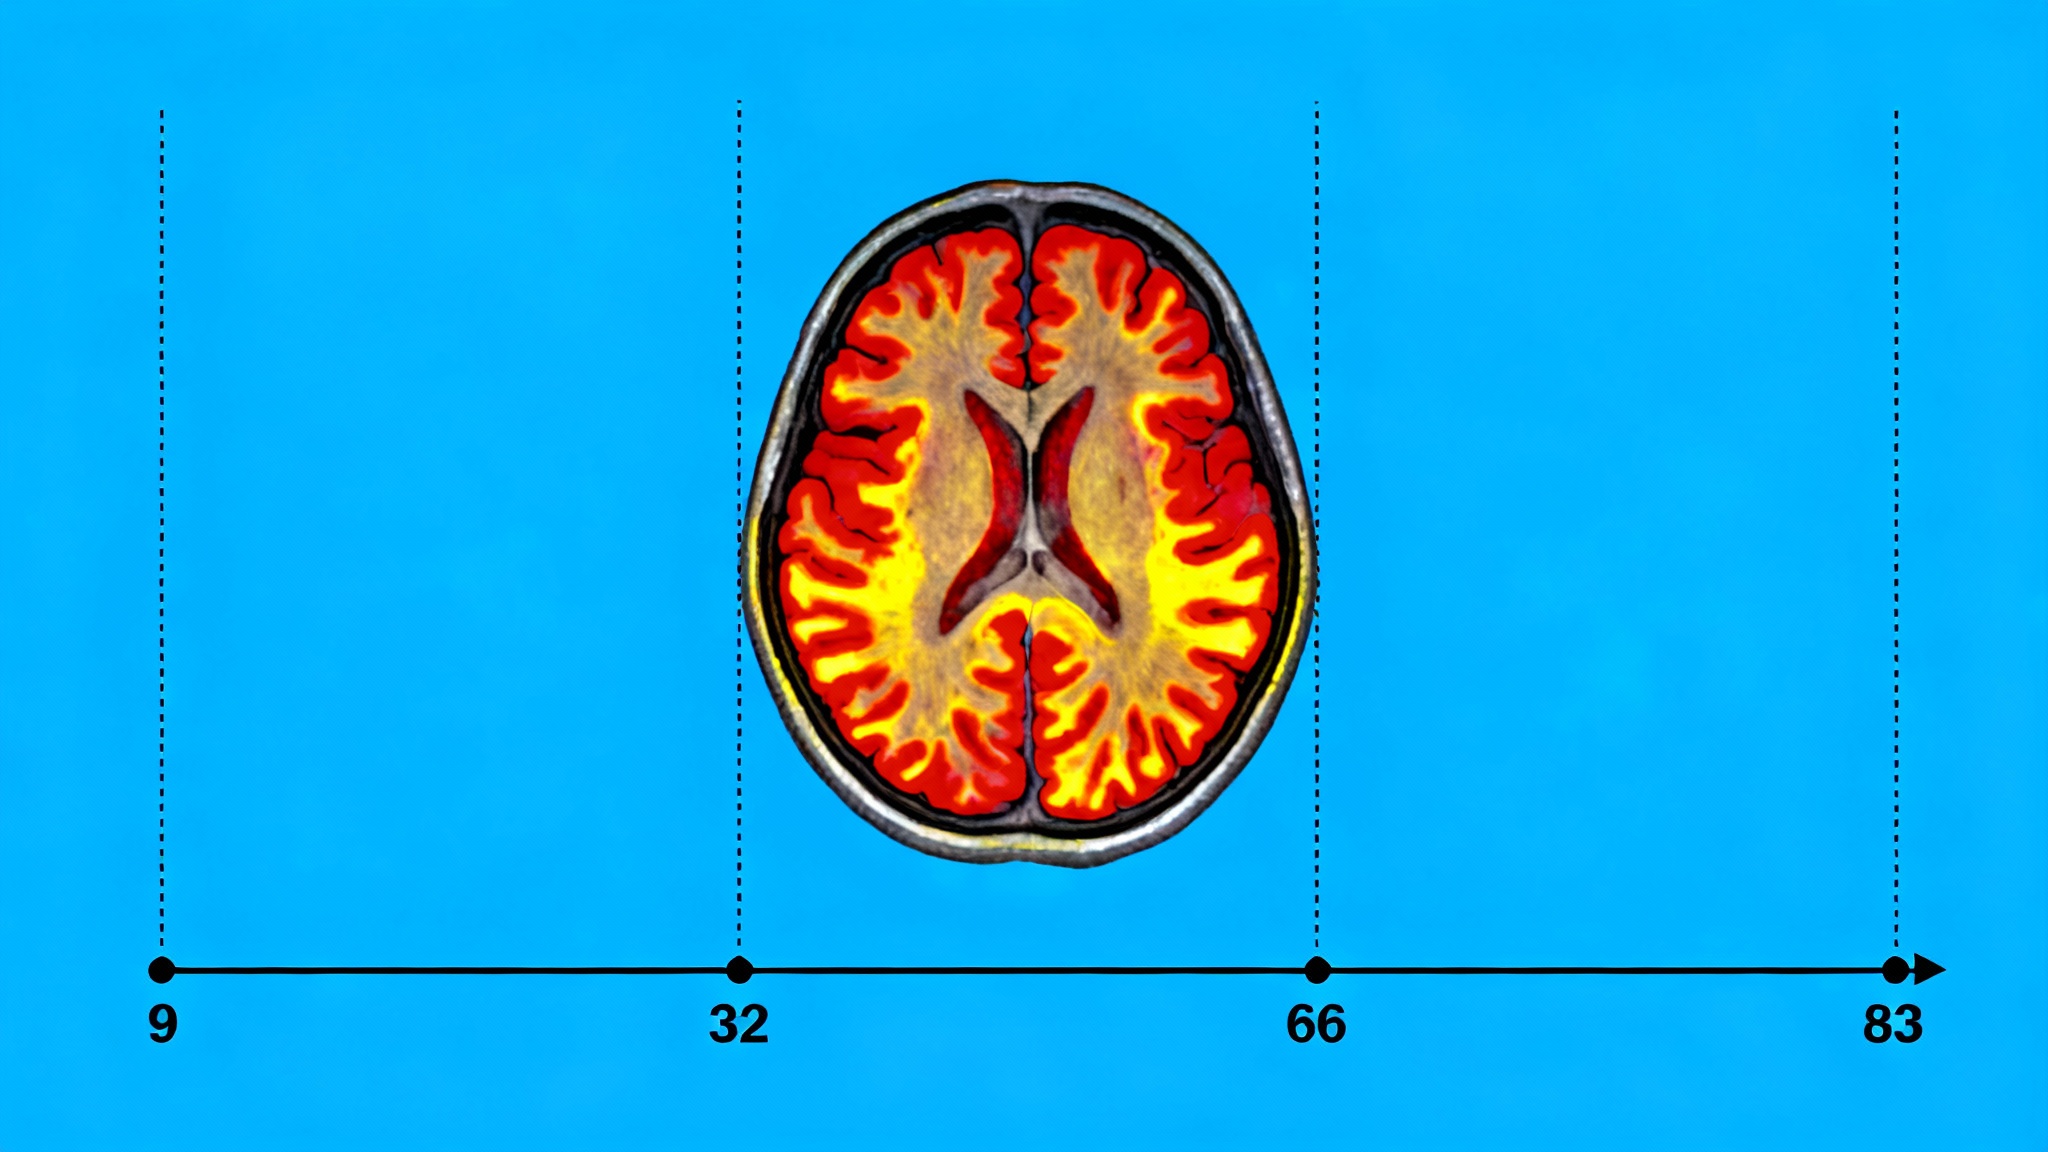

C’est en scrutant l’évolution de cette architecture interne qu’ils ont pu identifier les quatre tournants majeurs qui définissent les grandes époques de notre vie mentale : autour de 9 ans, 32 ans, 66 ans et, enfin, 83 ans.

Le premier changement radical survient vers l’âge de 9 ans, après la phase de « consolidation du réseau » propre à la petite enfance. Mais le constat le plus étonnant concerne ce que les chercheurs appellent l’adolescence prolongée. Selon cette étude, la phase d’optimisation cognitive, où les connexions sont les plus efficaces et la communication neuronale la plus rapide, perdure bien au-delà de la vingtaine.

Ce développement n’atteindrait son apogée qu’au début de la trentaine. À 32 ans, précise l’étude, on atteindrait même le « tournant topologique le plus important » de notre existence. Notre cerveau reste donc, structurellement parlant, très dynamique jusqu’à ce moment crucial.

Ce n’est qu’après ce pic que l’architecture neuronale passe véritablement en « mode adulte ». Vers 32 ans s’amorce ainsi la période la plus longue du cycle de vie cérébral, s’étendant sur plus de trois décennies.

Les choses se reconfigurent une troisième fois aux alentours de 66 ans. C’est l’entrée dans la phase de « vieillissement précoce » de l’architecture cérébrale. Le Dr Alexa Mousley, l’une des auteurs, note que cette réorganisation progressive des réseaux culmine au milieu de la soixantaine, un âge souvent marqué par une vulnérabilité accrue aux affections touchant le cerveau, telle que l’hypertension.

Le dernier tournant, celui du « vieillissement tardif », ne s’opère qu’autour de 83 ans, marquant la dernière étape observée par les scientifiques.